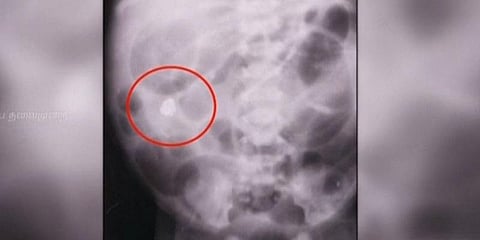

பெருஞ்சேரியைச் சேர்ந்த சரவணன் என்பவரது மனைவி சுமித்ராவுக்கு, கடந்த 16 ஆம் தேதி மயிலாடுதுறை அரசு மருத்துவமனையில் பெண் குழந்தை பிறந்தது. பிறந்த குழந்தையின் வயிறு வீங்கியது போல இருந்ததால், தீவிர சிகிச்சைப் பிரிவில் வைத்து மருத்துவர்கள் ஒரு வாரம் சிகிச்சையளித்தனர். அப்போது குழந்தை கறுப்பு நிறத்தில் வாந்தி எடுத்ததோடு, உடல்நலம் மிகவும் மோசமானது.

இதுகுறித்து குழந்தையின் குடும்பத்தினரிடம் மருத்துவர்கள் கேட்டபோது, நாட்டு வைத்திய முறைப்படி பாதரசத்தை வெற்றிலை சாற்றில் கலந்து கொடுத்ததாக கூறியுள்ளனர். பின்னர் கூடுதல் கவனம் எடுத்து சிகிச்சை அளித்த மருத்துவர்கள், மேல் சிகிச்சைக்காக தஞ்சை அரசு மருத்துவமனைக்கு அனுப்பினர். கடந்த 2 நாள்களாக குழந்தைகள் நல தீவிர சிகிச்சை பிரிவில், குழந்தைக்கு சிகிச்சை அளிக்கப்பட்டு வருகிறது. குழந்தை தற்போது அபாய கட்டத்தைத் தாண்டியிருப்பதாக மருத்துவர்கள் கூறுகின்றனர்.